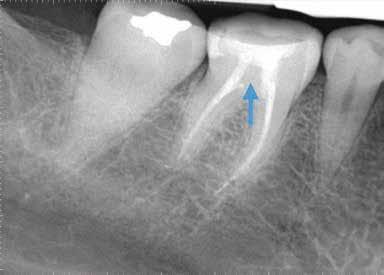

CÉLZOTT ENDODONCIAI MIKROSEBÉSZET

1. a-n. ábrák: Preoperatív CBCT-felvétel a bal alsó 6-os (3.6) fogról. Az axialis (a), coronalis (b) és sagittalis (c) nézeteken a mezialis és distalis gyökerek apicalis harmada körül sugáráteresztő zóna és ép buccalis corticalis csont látható. Egy olyan sablont terveztünk, amely jelezte a csontablak határait az apicalis terület pontos elérése érdekében (d). A mikrosebészeti bevatkozás során a sablont a helyére illesztettük (e), a csontablak határait megjelöltük (f) egy Piezotome CUBE LED kézi-darabba fogott fűrésszel, majd kivágtuk és eltávolítottuk (g és h) az apicalis területhez történő hozzáférés, illetve a mezialis és distalis gyökerek rezekciójának, retrográd preparációjának és retrográd gyökértömésének elvégzése érdekében (i). Végezetül a csontablakot visszaillesztettük és kollagén szivaccsal stabilizáltuk (j). A műtét után közvetlenül készített röntgenfelvétel a 3.6-os fogról (k). A kétéves kontroll során készített CBCT-felvétel: axialis (l), coronalis (m) és sagittalis (n) nézetek.

Egy 63 éves páciens korábban már kezelt bal alsó első nagyőrlőfogából (3.6) eredő mérsékelt fájdalom miatt kereste fel rendelőnket. A kórtörténetében panasza szempontjából releváns információ nem szerepelt. Az elkészült CBCT-felvételen a korábbi kezelések során észre nem vett, jelenleg feltáratlan meziobuccalis csatornát, valamint a mezialis és distalis gyökerek körül kialakult periapicalis elváltozást, és ezt a léziót borító intakt buccalis corticalis csontlemezt láttunk.

Klinikai vizsgálat során vertikális kopogtatási érzékenységet jelzett. A fog körül mérhető szondázási mélység és a fogmobilitás fiziológiás volt. A CBCT-felvételen nem észleltünk a csontos regeneráció megindulására utaló jeleket (1. a–c. ábrák). A korábban gyökérkezelt, gyökértömött és revideált 3.6-os fog esetében az alábbi diagnózis került felállításra: periodontitis periapicalis symptomatica. A panaszokat okozó fog további ellátása során navigált endodonciai mikrosebészetet kívántunk alkalmazni. Az alsó állcsontról intraorális szkent (TRIOS, 3Shape) készítettünk, és a felszíni topográfiát tartalmazó STL fájlt, valamint a CBCT-felvétel készítése során nyert DICOM fájlokat a Blue Sky Bio szoftver segítségével egyesítettük. A sebészi sablon megtervezésére az így kapott háromdimenziós képet használtuk. A sablon kialakítása során arra törekedtünk, hogy a sablon egyértelműen meghatározza a gyökércsúcsi terület eléréséhez szükséges csontablak határait (1. d. ábra)